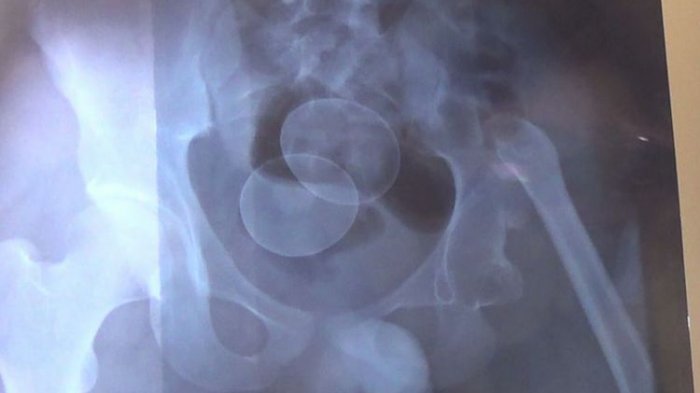

Hasil rontgen RSUD Syech Yusuf Sungguminasa, Kabupaten Gowa, Sulawesi Selatan, menunjukkan letak dua butir telur di dalam tubuh Akmal, Senin (19/2/2018). (KOMPAS.COM/ABDUL HAQ)

Sebelumnya, pihak rumah sakit berhasil mendapatkan foto rontgen letak dua butir telur di dalam tubuh Akmal.